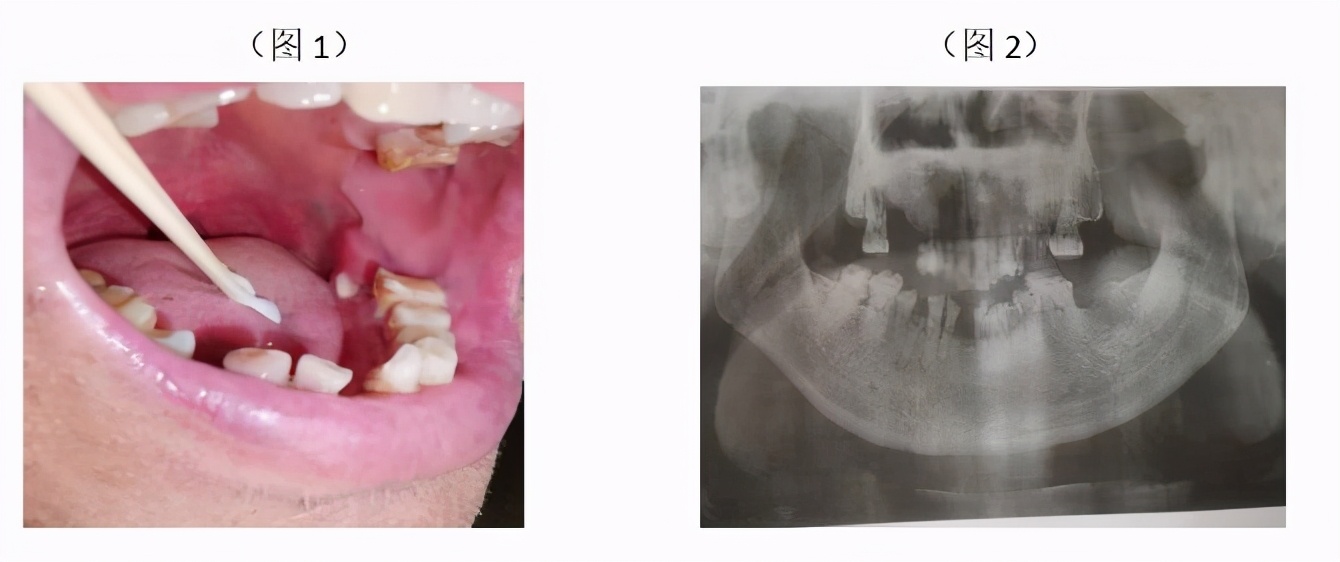

当日患者就诊时左下后牙牙龈已无明显脓性分泌物,检查见:患者左下第二磨牙区舌侧牙龈见类似牙体组织样凸起,较圆钝,质地硬较粗糙,牙龈稍红无明显分泌物,左下第二磨牙缺失,口内情况如图1,拍摄口腔全景片如图2示:(左下第二磨牙区牙槽骨低密度改变,牙槽窝未见牙体组织影像)。详细追问患者病史:诉外院诊断前列腺癌病史3年余,每月注射唑来膦酸注射液预防瘤骨转移、否认放疗史,一年前左下后牙松动伴疼痛牙齿自行脱落特未做特殊处理。故到此问题豁然开朗,患者长期服药双磷酸盐药物否认放疗史,颌骨病变发生前有牙齿脱落史,治疗建议:相关科室会诊后,停用双磷酸盐药物3-6个月后才考虑去除死骨及病变组织。常规医嘱,根据患者症状:局部漱口水含漱或全身抗炎止痛对症处理。